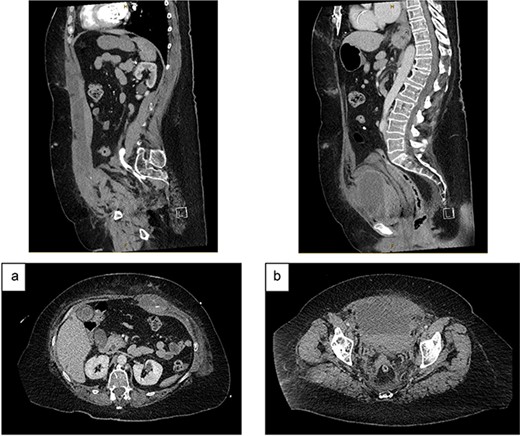

On Day 2, she became haemodynamically unstable with heart rate 150 bpm, systolic blood pressure 84 mmHg and a haemoglobin drop to 84 g/L. She was given oral Vitamin K and transfused packed red blood cells (PRBC) and fresh frozen plasma. CT angiography showed an increased RSH (61x36x301mm) with multiple foci of arterial enhancement, and a large pelvic extraperitoneal haematoma (119x81x121mm) displacing the urinary bladder posteriorly with active extravasation posterior to the left superior pubic ramus (Fig. 2). The Surgical team held extensive discussions with Interventional Radiology, Intensive Care, Haematology, Cardiology and Urology. The balance was in favour of ongoing conservative management due to (i) the thrombosis risk associated with discontinuing anticoagulation and (ii) the technical difficulty and risks of embolisation in an anticoagulated patient with multiple foci of arterial extravasation.

CT angiography (portal venous phase): (a) increased size of RSH and ongoing active extravasation – sagittal (top) and axial (bottom) views. (b) Extraperitoneal haematoma compressing and displacing urinary bladder – sagittal (top) and axial (bottom) views.